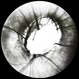

- nerve, optic nerve pit, visual field defect, Humphrey visual field, amblyopia, hemifield

- Kim Barrett C.O.A. Retina Specialist of Michigan, Grand Rapids, MI

Fundus camera

Optos California - Description

- A 14-year-old male presented with vision loss and VF defect. Patient was treated for presumed amblyopia with patching since age 4. He has had neurologic care for post traumatic skull fracture and brain bleed in 2012. Patient has a superior hemifield defect OS on HVF. IOP's WNL. There are vessels emanating from the optic pit OS. Patient is at risk of serous detachment. Current VA 20/20-2+2